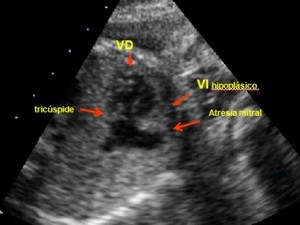

Ventrículo único tipo atresia tricúspide

(ver figura y video del ventrículo único). Se observa un ventrículo derecho con cavidad (color negro) casi inexistente o no desarrollado y que queda reducido una pequeña cámara situada debajo de la aurícula derecha (ventrículo hipoplásico). Entre éste y la aurícula derecha vemos una línea gruesa de color blanco que corresponde a la válvula tricúspide, que en este caso no se ha perforado y aparece como una membrana fibrosa que carece de función (atresia tricúspide). El ventrículo izquierdo tiene una cavidad grande (color negro) y ocupa el espacio teórico de los dos ventrículos, conformándose como el único funcionante de los dos (ventrículo único). Existen otras formas anatómicas de corazón univentricular; la atresia tricúspide es la más común.

Cuatro Cámaras, Ventrículo único